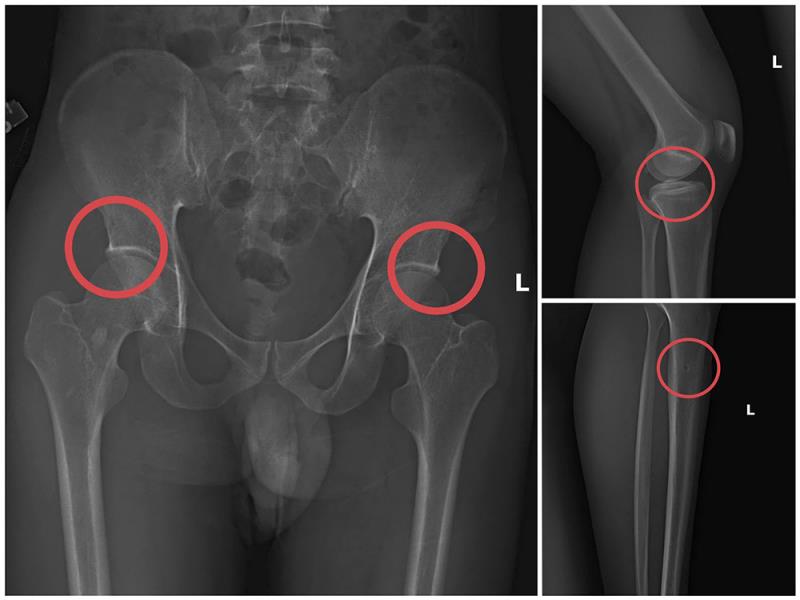

Tại đây, đối tượng Châu tiêm thuốc mê vào tĩnh mạch tay phải của người mua bảo hiểm, sau khoảng 1 phút họ bị mê đi thì Châu sẽ dùng búa và kim tiêm đục, đâm vào vùng cơ thể đã thống nhất từ trước để tạo vết tổn thương trên xương cho nứt, vỡ (thường sẽ làm rạn nứt, vỡ vùng xương chậu, xương đùi…).

Tiếp đó, đối tượng Châu đợi khoảng 10-20 phút khi thuốc mê hết tác dụng, những bệnh nhân tỉnh lại, anh ta hướng dẫn những người này tạo ra những vụ tai nạn tự nhiên để được hưởng bảo hiểm như: Bị điện giật ngã làm nạn nhân gãy xương chậu, đi suối ngã gãy chân... rồi nhờ người đưa đến Trung tâm y tế, bệnh viện khám và điều trị lấy bệnh án.